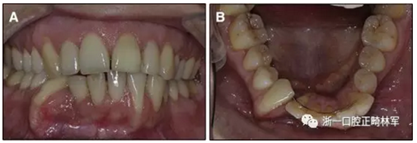

此外,有幾篇關(guān)于長期使用固定保持器后出現(xiàn)并發(fā)癥的報道被發(fā)表。在嚴重情況下,“非設(shè)計性主動保持器”幾乎可以完全將牙根部移出牙槽骨(圖1)。